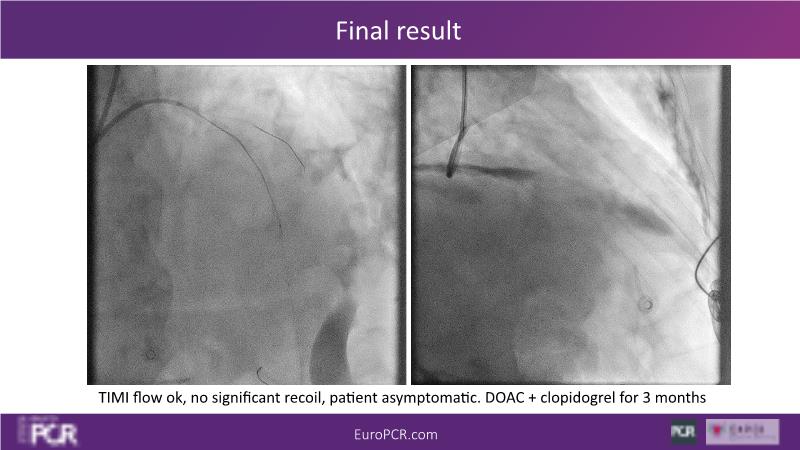

Through the study of two cases, this session examines the need for stenting bifurcation lesions and the role of DEB technology in avoiding stent-related complications in long diffuse disease. It emphasizes the benefits of SELUTION SLR balloons for de novo lesions, discussing how sustained limus release technology can broaden DEB indications and reduce metal usage, understanding the limitations of DES and the emerging role of DEB with sustained limus release, and learning how to identify dissections that can be left unstented.

- To learn how to identify dissections that can be left unstented